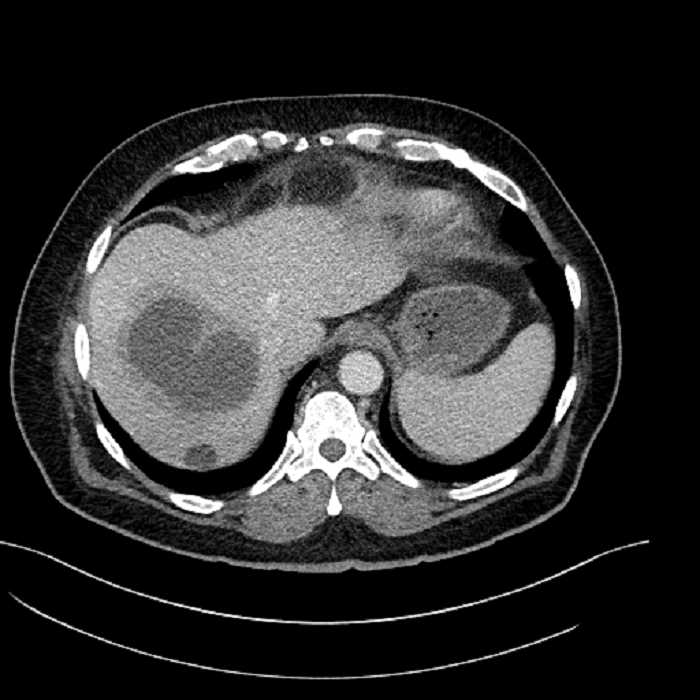

• Large fluid density structure in hepatic segments 7 and 8 measuring 10 x 7 x 7 cm with internal septation and circumferential ill-defined low density compatible with edema

• Peripherally enhancing subcapsular collections along the anterior margin of the left hepatic lobe measuring 3 x 1 cm and 2 x 1 cm

• Clearly marginated fluid density structure in segment 7 and several other scattered tiny hypodensities, which likely represent cysts

• Hepatic abscess

Acute sigmoid diverticulitis complicated by a small contained perforation and a large abscess in the right hepatic lobe. Additional small subcapsular abscesses along the anterior margin of the left hepatic lobe.

• The classic CT imaging appearance is a double target sign with internal low density surrounded by an internal enhancing rim (capsule) and a low density external rim (edema)

Hepatic abscess showing the double target sign with low density internally surrounded by a thin inner enhancing rim (red arrow) and ill-defined outer low density rim (yellow arrow). Blue arrow indicates an internal septation. Red arrows: additional smaller subcapsular abscesses. Red arrow: focal contained perforation associated with diverticulitis.